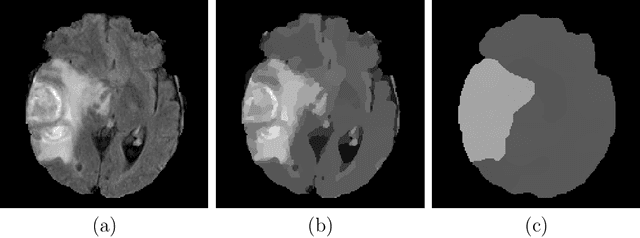

Abstract:We address the generalization behavior of deep neural networks in the context of brain tumor segmentation. While current topologies show an increasingly complex structure, the overall benchmark performance does improve negligibly. In our experiments, we demonstrate that a well trained U-Net shows the best generalization behavior and is sufficient to solve this segmentation problem. We illustrate why extensions of this model cannot only be pointless but even harmful in a realistic scenario. Also, we suggest two simple modifications (that do not alter the topology) to further improve its generalization performance.